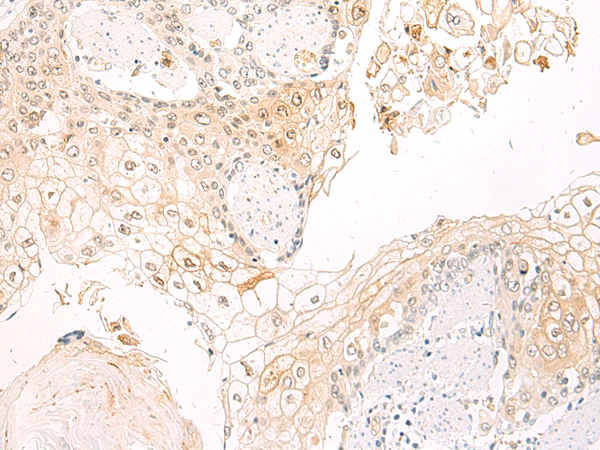

IHC positive control: |

Human esophagus cancer |

IHC Recommend dilution: |

50-100 |